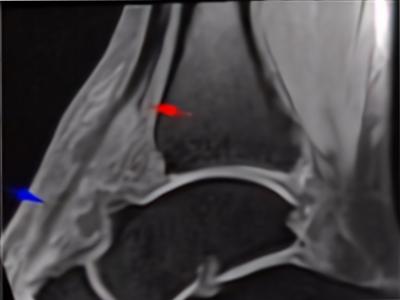

Figure 1: Sagittal T1 fat suppresion image of the ankle showed tear of the TA tendon at the level of distal tibial (red arrow) with the remaining tendon exhibited high signal intensity (blue arrow) till its insertion to the navicular base.